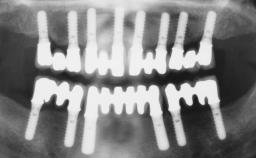

Conventional Loading of Eight Implants in the Maxilla and Final Restoration with a Full-Arch Gold-Ceramic FDP

# of Implants 8

Type of Implants One-Piece

Defining Characteristics Fully edentulous upper jaw to be rehabilitated with four or more implants

Bone Volume Deficient vertically or deficient vertically AND horizontally